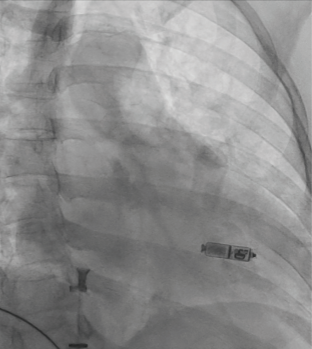

Video 3. Fluoroscopic image status post successful laser lead extraction of the entire dual-chamber pacemaker system due to fungal endocarditis on pacemaker lead. Vacuum aspiration device in the right atrium with percutaneous debulking of vegetation under TEE guidance.